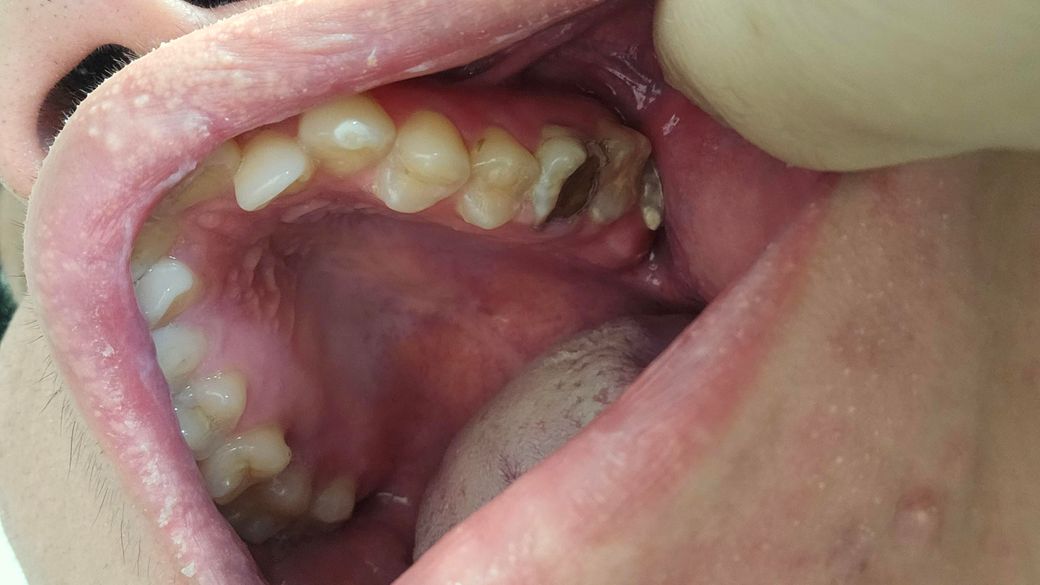

제가 이사진찍히이빨상태 이렇게되는데요 다음주 토요일 갔도 치료할수있나요 알려주세요

• 2번 째 사진

치아 상태가 좋아 보이진 않습니다. 치료는 엑스레이를 찍어보고 치아 상태를 정확히 파악하고 나서 결정해야될것같습니다. 빨리 가셔서 치료를 받아보세요.

사진으로 봤을 경우에는 이미 충치가 많이 진행된것으로 보입니다.

빠른치료가 필요할것으로 보이며 충치가 치아의 뿌리 끝까지 진행이 되었을 경우 발치를 해야 할수 있습니다.

2. 충치가 커서 발치 가능성도 있어보입니다.